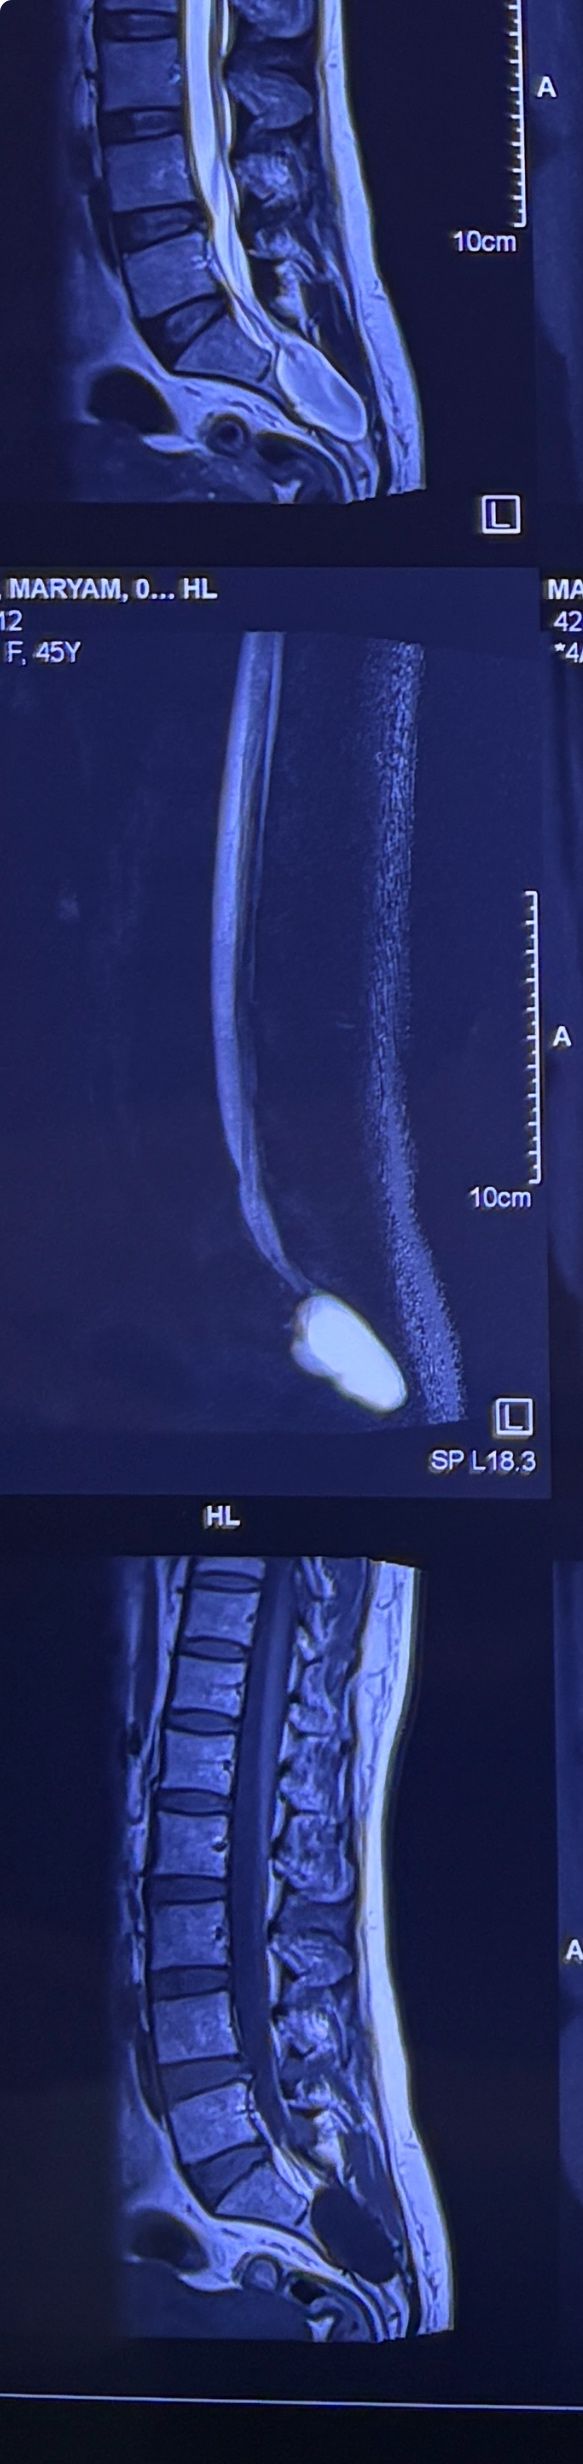

46 years old female patient presented to my clinic yesterday june 1/2025 with LBP and radicular L leg pain for several months which hasn’t responded to physio 2 neurosurgeons have visited her and didn’t suggest any surgery Neurological exam was unremarkable please see her mri/ emg/ncv and her huge tarlov cyst and possible L IVF L4-5 hyperbulge I ordered sacrum mri and ct scan and new emg/ncv and asked her with her sacral Ct scan and MRI first sees another two famous neurosurgeons and see if that large cyst is the reason for her pain if not i can work on her L4-S1 area Do you think her radicular pain can originate from her large cyst in sacrum? Do you consider surgery and removing her sacral cyst?

32 years female patient presented to my office one year ago with moderate cervical pain and R. Arm pain ,mild LBP with no radicular pain. Her mri in C/s had few bulges and few segmentsl dysfunctions

Her lumbar mri showed Contained R. Para. L5-S1 extrusion

She got treatment just for her neck and exercises for her low back. Few months later had lumbar disc surgery

Few days ago on may on june 08/2025, presented with severe LBP and no radicular pain

I have post her lumbar MRI before and after surgery. I consulted with a neurosurgeon at our clinic and he said doesn’t need another surgery because doesn’t have radicular pain or neurological deficits

For her pain i have started to do mild decompression by Cox and DTS and acupuncture, no adjustment whatsoever.

Please mention what differences you see before and after surgery